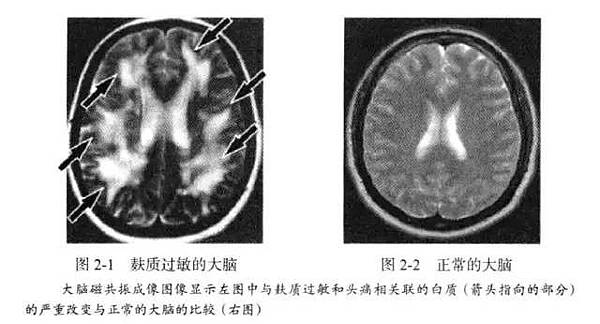

乳糜瀉是極端的麩質過敏,估計有高達1/30的人患有此病,特別是北歐後裔。早在一個世紀前,醫生們就發現乳糜瀉與神經失調之間有關聯,但他們認為可能是腸道吸收不好引起對大腦的營養問題,直到進入本世紀以來,研究者發現乳糜瀉患者同時伴隨著認知功能下降,而停止麩質食品後,則又慢慢恢復,研究者意識到是麩質蛋白引起了炎症因數,而後者導致腦部問題。請看下麵一組對照圖。

研究表明,56%的慢性頭痛患者對麩質過敏,30%患有乳糜瀉。大腦核磁掃描也發現麩質過敏的頭痛患者其大腦白質變化異常,這是因為炎症所致。在採用無麩質飲食後,很多人都得到了改善,還有一部分人的頭痛完全消失。